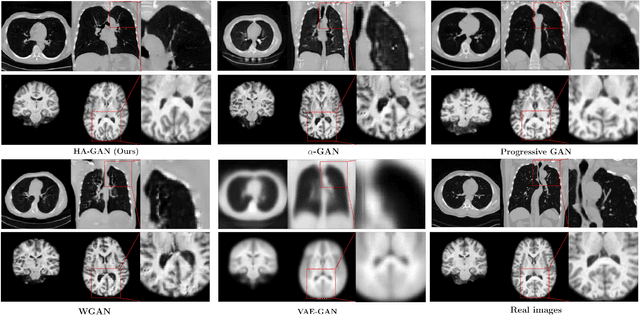

Abstract:Generative Adversarial Networks (GAN) have many potential medical imaging applications, including data augmentation, domain adaptation, and model explanation. Due to the limited embedded memory of Graphical Processing Units (GPUs), most current 3D GAN models are trained on low-resolution medical images. In this work, we propose a novel end-to-end GAN architecture that can generate high-resolution 3D images. We achieve this goal by separating training and inference. During training, we adopt a hierarchical structure that simultaneously generates a low-resolution version of the image and a randomly selected sub-volume of the high-resolution image. The hierarchical design has two advantages: First, the memory demand for training on high-resolution images is amortized among subvolumes. Furthermore, anchoring the high-resolution subvolumes to a single low-resolution image ensures anatomical consistency between subvolumes. During inference, our model can directly generate full high-resolution images. We also incorporate an encoder with a similar hierarchical structure into the model to extract features from the images. Experiments on 3D thorax CT and brain MRI demonstrate that our approach outperforms state of the art in image generation, image reconstruction, and clinical-relevant variables prediction.